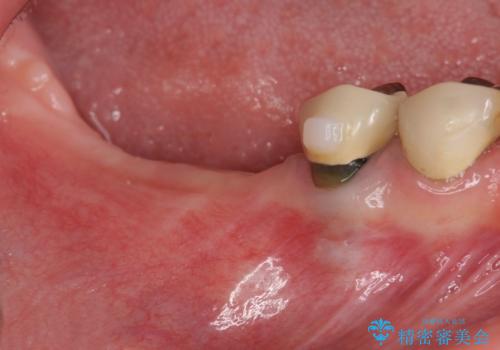

- 虫歯が多く、全体的な歯の検診を希望され当院に来院されました。

X線写真検査より、クラウンや銀歯の下で歯に大きな虫歯が発生し、抜歯を余儀なくされる状況でした。

虫歯に伴い歯槽骨の吸収も見られたので造骨後、インプラントを用いて咬合機能を回復します。

また、機能後のインプラント周囲の清掃性を高めるため遊離歯肉移植術を行っています。